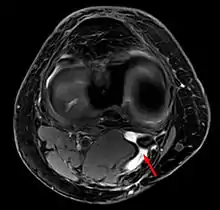

کیست بیکر (به انگلیسی: Baker's cyst) بیرون زدگی غشاء سینوویال در زانو است.بدین معنا که غشای سینوویال به سمت عقب و همچنین پایین زانو امتداد می یابد.چنین وضعیتی در عقب مفصل زانو منجربه افزایش مایع در غشای فتق یافته می گردد.گاهی این حالت به علت افزایش مایع در بورس عقب زانو ایجاد میشود.کیست با اندازههای مختلف در قسمت پشتی داخلی(خلفی داخلی)زانو دیده میشود که به خصوص در حالت ایستاده آشکارتر است[1].